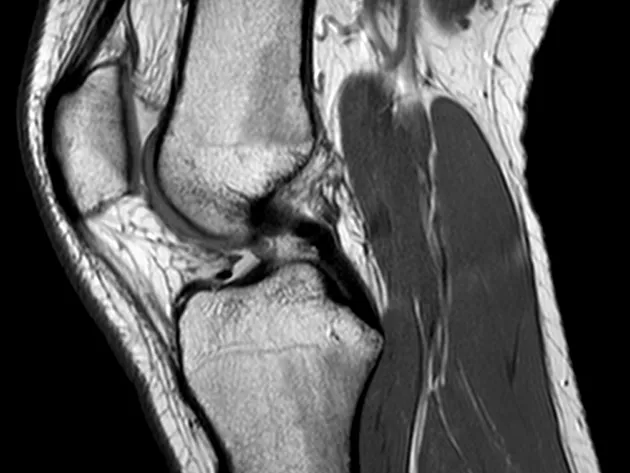

This module will help you to learn about the general and most common pathologies of the knee including traumatic and non-traumatic pathologies and the associated findings.

This module (5 MRI cases) will help you to learn complex anatomy of the knee including the femorotibial and patellofemoral joints. It will help you understand the biomechanics of injuries and recognise typical ligament and tendon injuries as well as associated meniscal, bone and cartilage abnormalities.